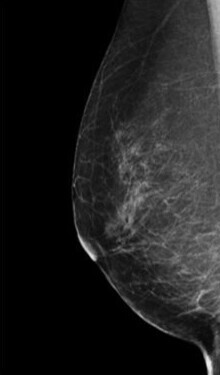

検査結果では、乳房の構成を以下4つに分類してお知らせします。

1.脂肪性

2.乳腺散在

3.不均一高濃度

4.極めて高濃度

3・4に該当する乳房は「高濃度乳房(デンスブレスト)」と呼ばれ、乳腺が白く映るためマンモグラフィのみでは異常が隠れてしまうことがあります。

そのため、マンモグラフィ検査と乳腺超音波検査の併用を強くおすすめします。

症状がなくても、高濃度乳房と判定された方は積極的な併用検診が早期発見につながります。